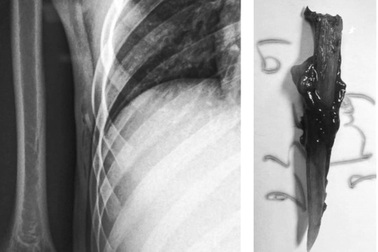

Xuống ao bắt cá, bé trai phải phẫu thuật vì ngạnh cá tra đâm vào ngựcBé trai 14 tuổi khi xuống ao bắt cá thì bị cá đâm vào người khiến ngạnh cá dính vào lồng ngực, phải nhập viện phẫu thuật.